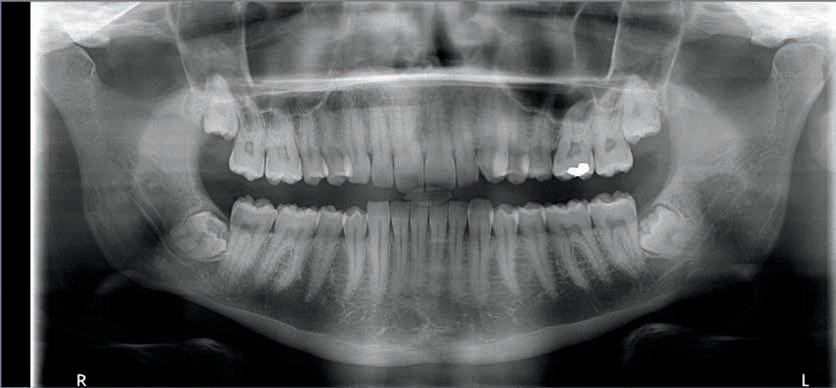

ABSTRACT

Atrofi af den posteriore mandibel byder på udfordringer, når en eller flere manglende tænder ønskes erstattet med en implantatbaseret protetisk restaurering. Behandlingsstrategi afhænger af flere faktorer, herunder dimensionerne af processus alveolaris samt beliggenheden af relevante anatomiske strukturer i mundbunden og mandiblen. Lokalisation af canalis mandibulae er således yderst vigtigt i forbindelse med implantatindsættelse i den atrofiske posteriore mandibel, da intraoperativ beskadigelse af n. alveolaris inferior vil medføre neurosensoriske forstyrrelser bl.a. svarende til hagen og underlæben. Omhyggelig behandlingsplanlægning inklusive radiologisk identifikation af canalis mandibulae er derfor afgørende for valg af relevant behandlingsmodalitet ved protetisk rehabilitering af den atrofiske posteriore mandibel og at gennemføre behandlingen med et forudsigeligt og sikkert behandlingsresultat med god langtidsprognose og mindst mulig risiko for komplikationer. I nærværende oversigtsartikel gennemgås forskellige metoder til vurdering af det tandløse område posteriort i mandiblen før implantatbehandling, herunder røntgenundersøgelse med særlig fokus på anvendelse af CBCT til lokalisering af canalis mandibulae.

GENERELLE BETRAGTNINGER I FORHOLD TIL BEHANDLINGSPLANLÆGNING før implantatindsættelse og relevante undersøgelsesmetoder til vurdering af processus alveolaris’ dimensioner med fokus på bredden er tidligere beskrevet i et nyligt publiceret temanummer af Tandlægebladet (1). Nærværende oversigtsartikel vil således udelukkende fokusere på de specielle udfordringer, der ses i forbindelse med implantatbehandling i den atrofiske posteriore mandibel, inklusive relevante kliniske og radiologiske undersøgelsesmetoder til identifikation af canalis mandibulae og omkringliggende anatomiske strukturer.

Behandlingsplanlægning i forbindelse med implantatindsættelse i den atrofiske posteriore mandibel med fokus på den radiologiske undersøgelse

Ved agenesi eller tandtab vil dimensionerne af processus alveolaris være mindskede som følge af manglende knogleudvikling eller fysiologisk resorption af den tandbærende del af kæben (2,3). Det er vist, at specielt bredden i kindtandsområdet i underkæben reduceres væsentligt efter fjernelse af tænder (4). Sufficient højde og bredde af processus alveolaris er en forudsætning for at sikre en ideel implantatplacering i kæbeknoglen og etablere grundlaget for en korrekt æstetisk og funktionel udformning af den efterfølgende protetiske erstatning med en god langtidsprognose. En mindsket afstand fra toppen af processus alveolaris til den øvre begrænsning af canalis mandibulae i forbindelse med tandtab fordrer derfor ofte anvendelse af kortere implantater eller genopbygning af processus alveolaris før eller i forbindelse med indsættelse af standardlængdeimplantater. Dimensionerne af processus alveolaris samt graden af atrofi har således væsentlig indflydelse på valg af behandlingsstrategi i den atrofiske posteriore mandibel.

En klassifikation af de tandløse kæber blev i 1988 foreslået af Cawood og Howell (5). Ifølge denne blev den tandløse posteriore mandibel inddelt i seks klasser baseret på graden af atrofi (Fig. 1). Når forholdene og pladsen er væsentligt kompromitterede i forhold til optimal indsættelse af implantater med en passende diameter og længde for den kommende protetiske restaurering, kan kirurgisk forbehandling eller alternative kirurgiske metoder være indicerede. Valget af kirurgisk teknik vil bl.a. afhænge af graden af atrofi. Forskellige behandlingsmodaliteter har tidligere været anvendt til implantatbaseret protetisk rehabilitering af den atrofiske posteriore mandibel,

inklusive indsættelse af korte implantater, sandwich-osteotomi, onlay autolog bloktransplantation, styret knogleregeneration, alveolær distraktions-osteogenese samt transposition eller lateralisering af n. alveolaris inferior (NAI). Imidlertid er den aktuelle afstand fra den øvre begrænsning af canalis mandibulae til toppen af processus alveolaris afgørende for valg af relevant behandlingsmodalitet (6).

De morfologiske karakteristika for den posteriore mandibel samt tilstedeværelsen af ”kritiske” anatomiske strukturer stiller væsentlige krav til behandleren, når implantatbehandlingen skal planlægges og udføres. Kendskab til anatomien, normalanatomiske variationer samt opmærksomhed på mu-

Cawood & Howell’s klassifikation af den tandløse posteriore mandibel

Fig. 1. Mandiblen inddelt i seks klasser: Klasse I, betandet posterior mandibel. Klasse II, umiddelbart efter tandudtrækning. Klasse III, velafrundet processus alveolaris med sufficient højde og bredde. Klasse IV, knivskarp processus alveolaris med sufficient højde og utilstrækkelig bredde. Klasse V, flad processus alveolaris med utilstrækkelig højde og bredde. Klasse VI, deprimeret processus alveolaris med varierende grad af basalt knogletab.

Fig. 1. The mandible graduated into six classes: Class I, dentate posterior mandible. Class II, immediately post extraction. Class III, well-rounded ridge form, adequate in height and width. Class IV, knife-edge ridge form, adequate in height and inadequate in width. Class V, flat ridge form, inadequate in height and width. Class VI, depressed ridge form, with some basalar loss evident. III IV VI